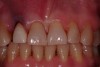

A 54-year-old, non-smoking woman presented with a root fracture at the maxillary right lateral incisor (Figure 1). The patient presented with a 10-mm pocket at the mid-facial probing depth, and a Grade 2 mobility. The preoperative peri-apical digital radiograph can be seen in Figure 2. A natural diastema existed on the distal aspect of the right maxillary incisor, and the patient did not wish to have this corrected. To hold the natural tissue emergence profiles throughout the treatment phase, the immediate implant placement and provisionalization procedure was chosen to treat the affected site. Before the procedure, an occlusal index and registration was taken so that when the retrofitting of the natural tooth shell was accomplished, the exact location of the natural tooth shell could be seated on the implant abutment at the time of implant placement (Figure 3). After administration of an appropriate local anesthetic, tooth No. 7 was removed by an atraumatic technique to preserve the natural soft tissue emergence profiles present pre-surgically (Figure 4). After tooth removal, debridement of the extraction socket was accomplished by curettage of the socket, followed by rotary instrumentation with a course #8 round diamond to ensure removal of all remnants of the periodontal ligament, granulation tissue, and localized debris. To aid in the debridement, the patient was started on a preoperative administration of Augmentin 875 mg, taken the day before treatment, and once again 1 hour before the surgical visit. The patient then continued this antibiotic course for a total of 10 days.

Figure 1  Pretreatment clinical view.

Figure 1